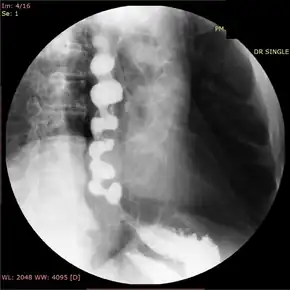

![]() | |

| Jackhammer esophagus with normal distal latency on esophageal high-resolution manometry | |